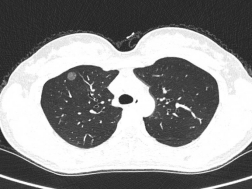

另外两位患者中,患者2,61岁男性曾有传统手术经历,患者3,29岁女性为年轻早癌患者。杨超教授分析了两位患者的病情特点,最终决定为两人实施国内领先的Tubeless单孔胸腔镜楔形切除术(无气管插管、无尿管、无引流管)。术后61岁男性反馈格外积极,男性患者直言:“上次手术疼得不敢动,这次当天就能走路!”;年轻女性患者则表示:“像睡了一觉,醒来几乎不疼,隔天就顺利出院了”。